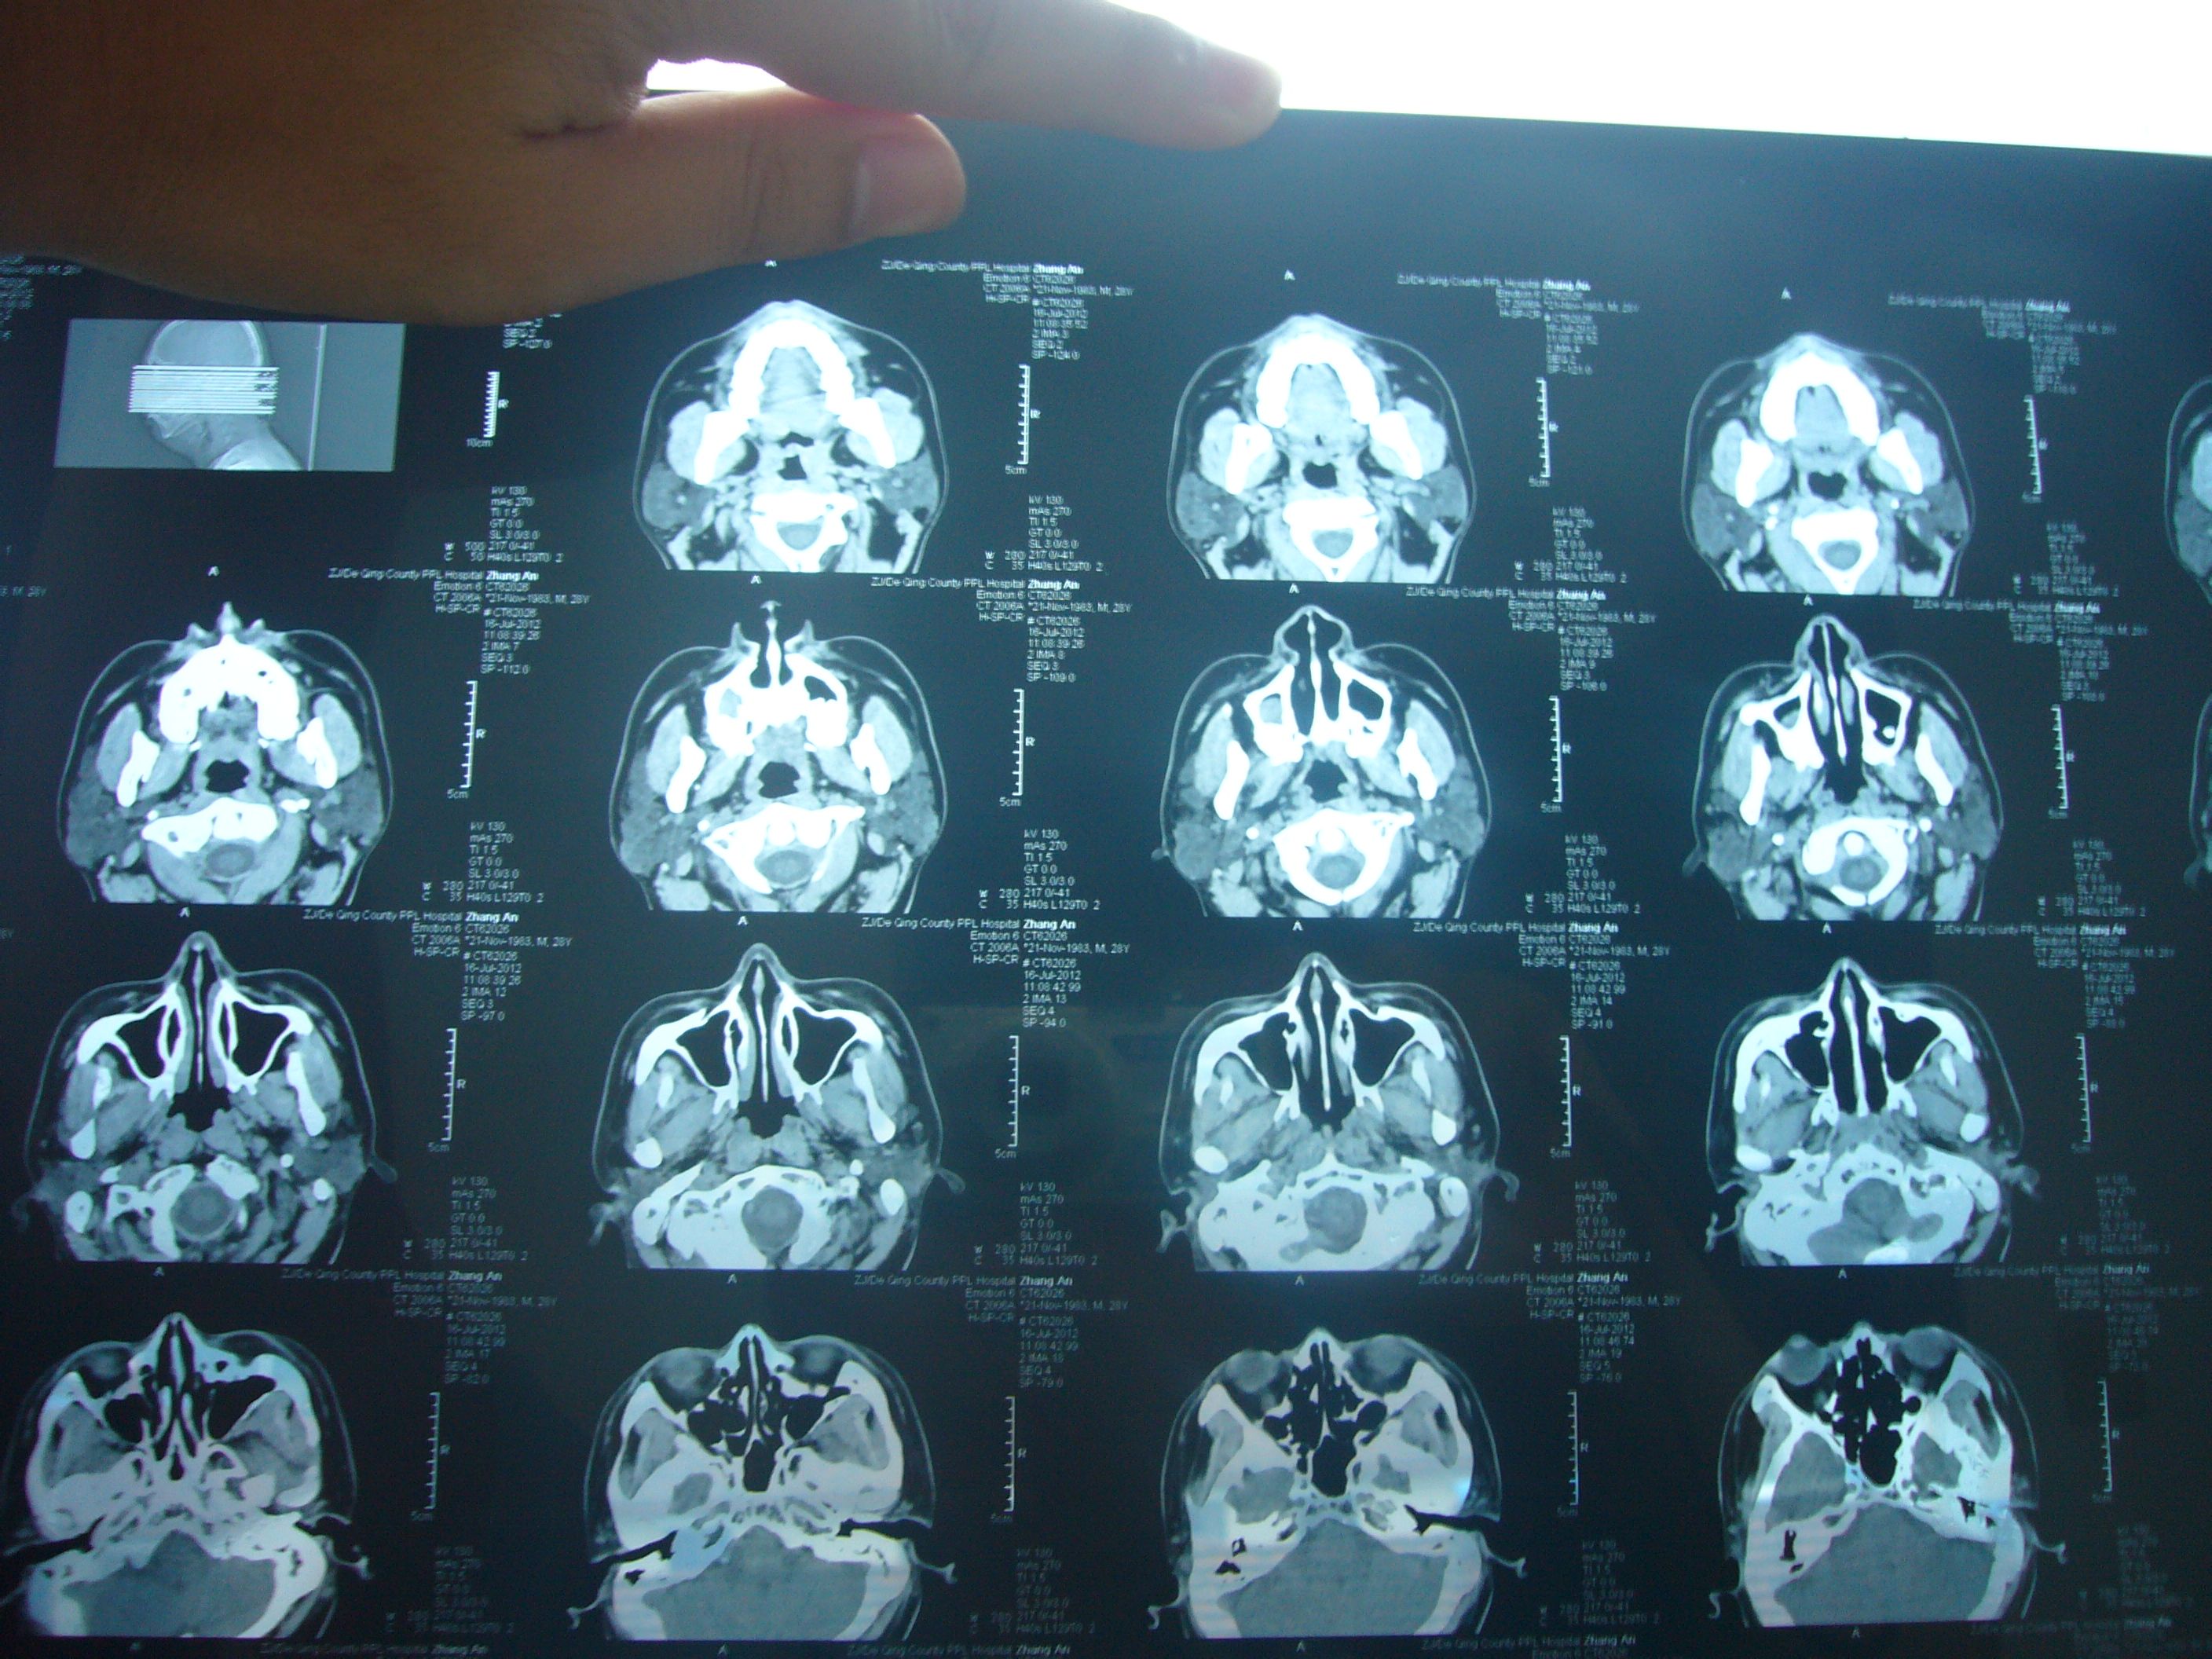

老师们好,我家有个亲戚拍了个鼻子ct,但是我水平有限,请帮忙看看片子

图片尺寸4752x3168